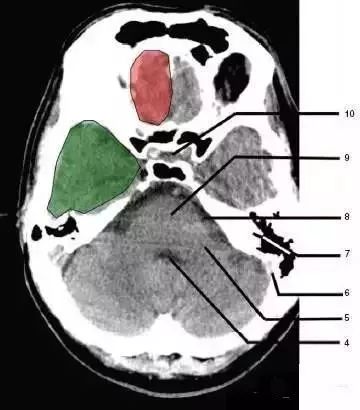

4、第四脑室(Fourth ventricle)

5、小脑中角(Middle cerebellar peduncle)

6、乙状窦(Sigmoid sinus)

7、颞骨及乳突气房(Petrous temporal bone and mastoid air cells)

8、桥小脑角(Cerebellopontine angle)

9、脑桥(Pons)

10、垂体窝(Pituitary fossa):绿色部分为颞叶(Temporal Lobe),浅红色部分为额叶(Frontal Lobe)